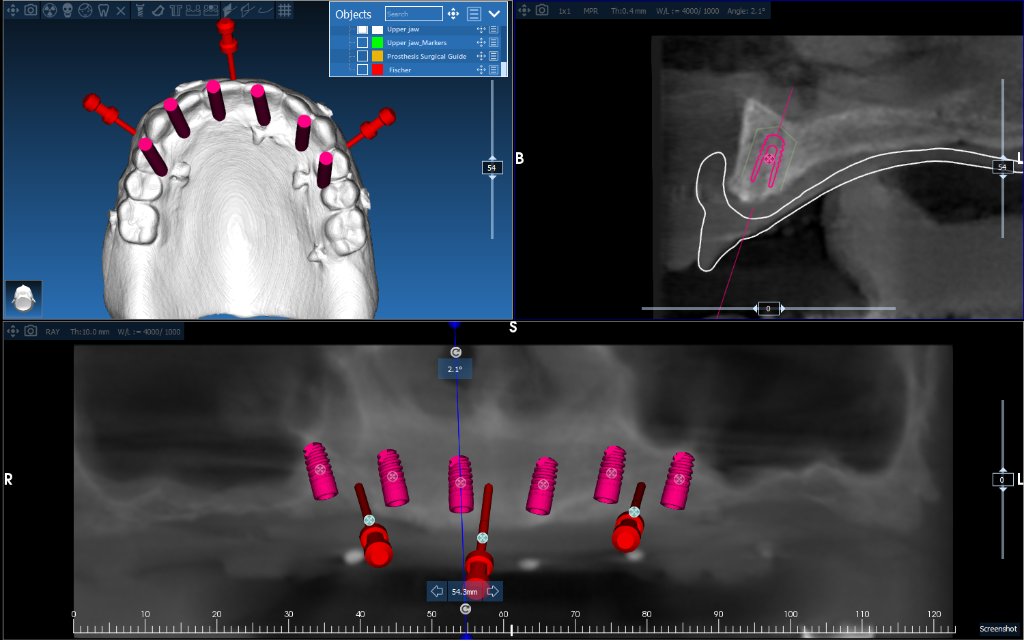

Full-Arch Implant Rehabilitation

All-on-4 surgical guide for complete upper arch restoration